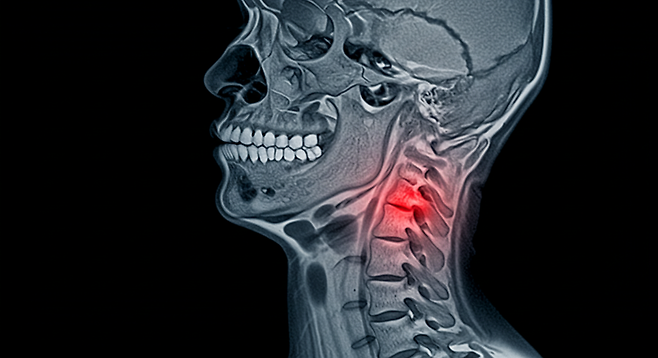

이런 증상이 반복되자 병원을 찾았고, 경추 신경 압박 진단을 받았다. 당신의 몸이 보내는 경고 신호를 제대로 읽고 있을까?

목디스크로 인한 신경 자극의 경우, 목을 뒤로 젖힐 때 증상이 심해지는 특징이 있다. 메니에르병이 의심될 땐 이명(귀울림)과 함께 회전성 어지러움이 동반되며, 특정 머리 위치에서 증상이 유발되는 BPPV(양성 발작성 체위 현훈)와 구분이 필요하다.

Case 1디자이너 C씨(34)는 모니터를 장시간 응시한 후 발생하는 두부 감각 이상을 호소했다. 경추 MRI에서 목뼈 5-6번 사이 신경 구멍이 좁아진 것이 원인으로 밝혀져 물리치료 8주 만에 호전됐다.

▶ 신경 추적 레이더경추 3D CT는 뼈 구조를 입체적으로 분석해 목디스크 유무를 0.1mm 단위까지 포착한다. 신경전도검사에서는 손가락에 전극을 부착해 신경 신호 전달 속도를 측정, 압박 부위를 특정한다.